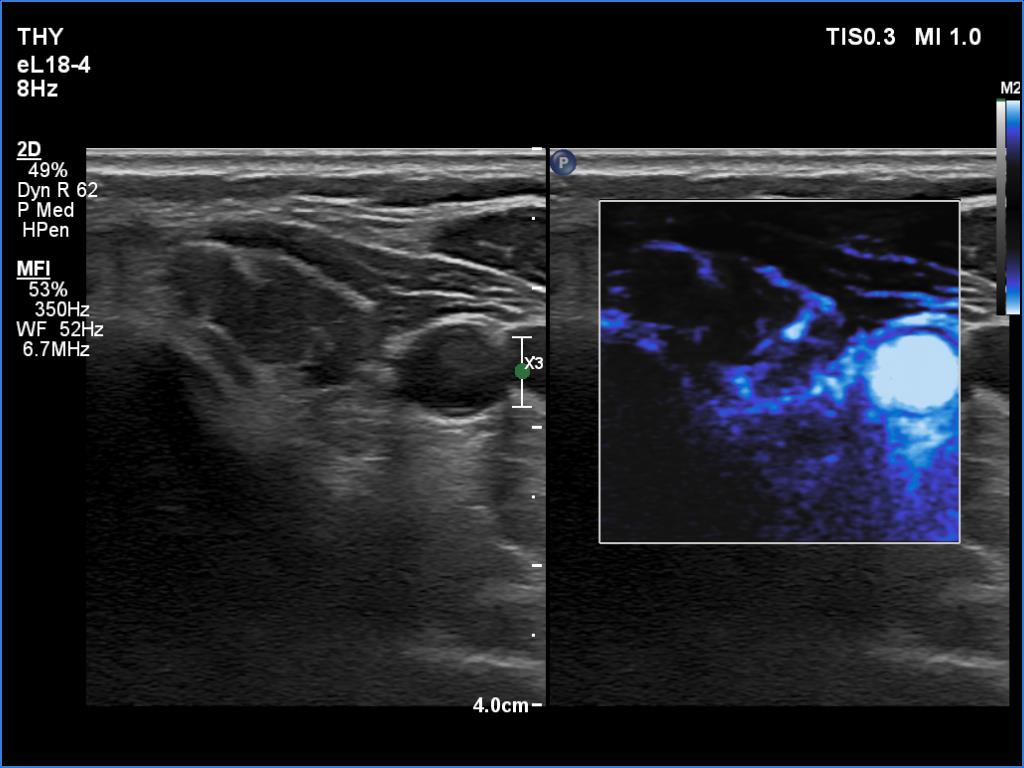

Right lobe, longitudinal scan

Left lobe, transverse scan, microflow imaging. There are vessels only according to the connective tissue branches.